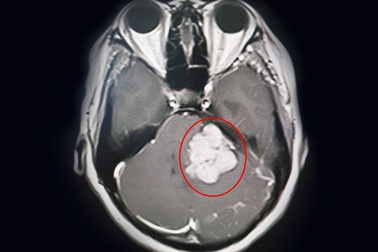

Đau đầu, mất thính lực vì khối u như quả trứng trong nãoSau thời gian dài bị đau đầu, ù tai, điếc dần bệnh nhân rơi vào tình trạng liệt nửa mặt, đau dữ dội. Tại bệnh viện, bác sĩ xác định người bệnh có khối u lớn như quả trứng trong góc cầu tiểu não.